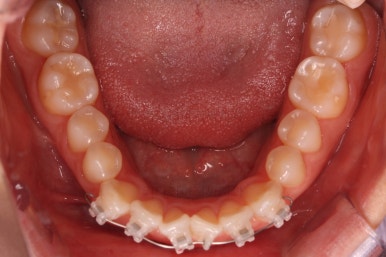

부산나비앞니교정 키다리아저씨치과에 처음 내원하셨을 당시의 입 안 모습입ㄴ디ㅏ.

보시다시피 위아래 정중앙에 있는 치아가 V자 형태로 꺾여있었어요.

흔히 "나비치아", "나비앞니"라고 표현을 하는데 나비 날개짓을 하듯이 꺾여 있다고 그렇게 부릅니다.

어금니쪽의 맞물림은 굉장히 양호한 편이였기 때문에 부분교정에 딱 알맞는 경우였어요.